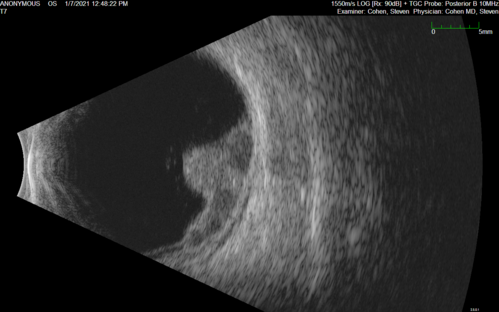

Class 2 choroidal melanoma

48 year old man with no visual complaints referred by optometrist.

Brachytherapy was done and biopsy showed a class 2 melanoma. 2 years later the patient developed liver metastases.